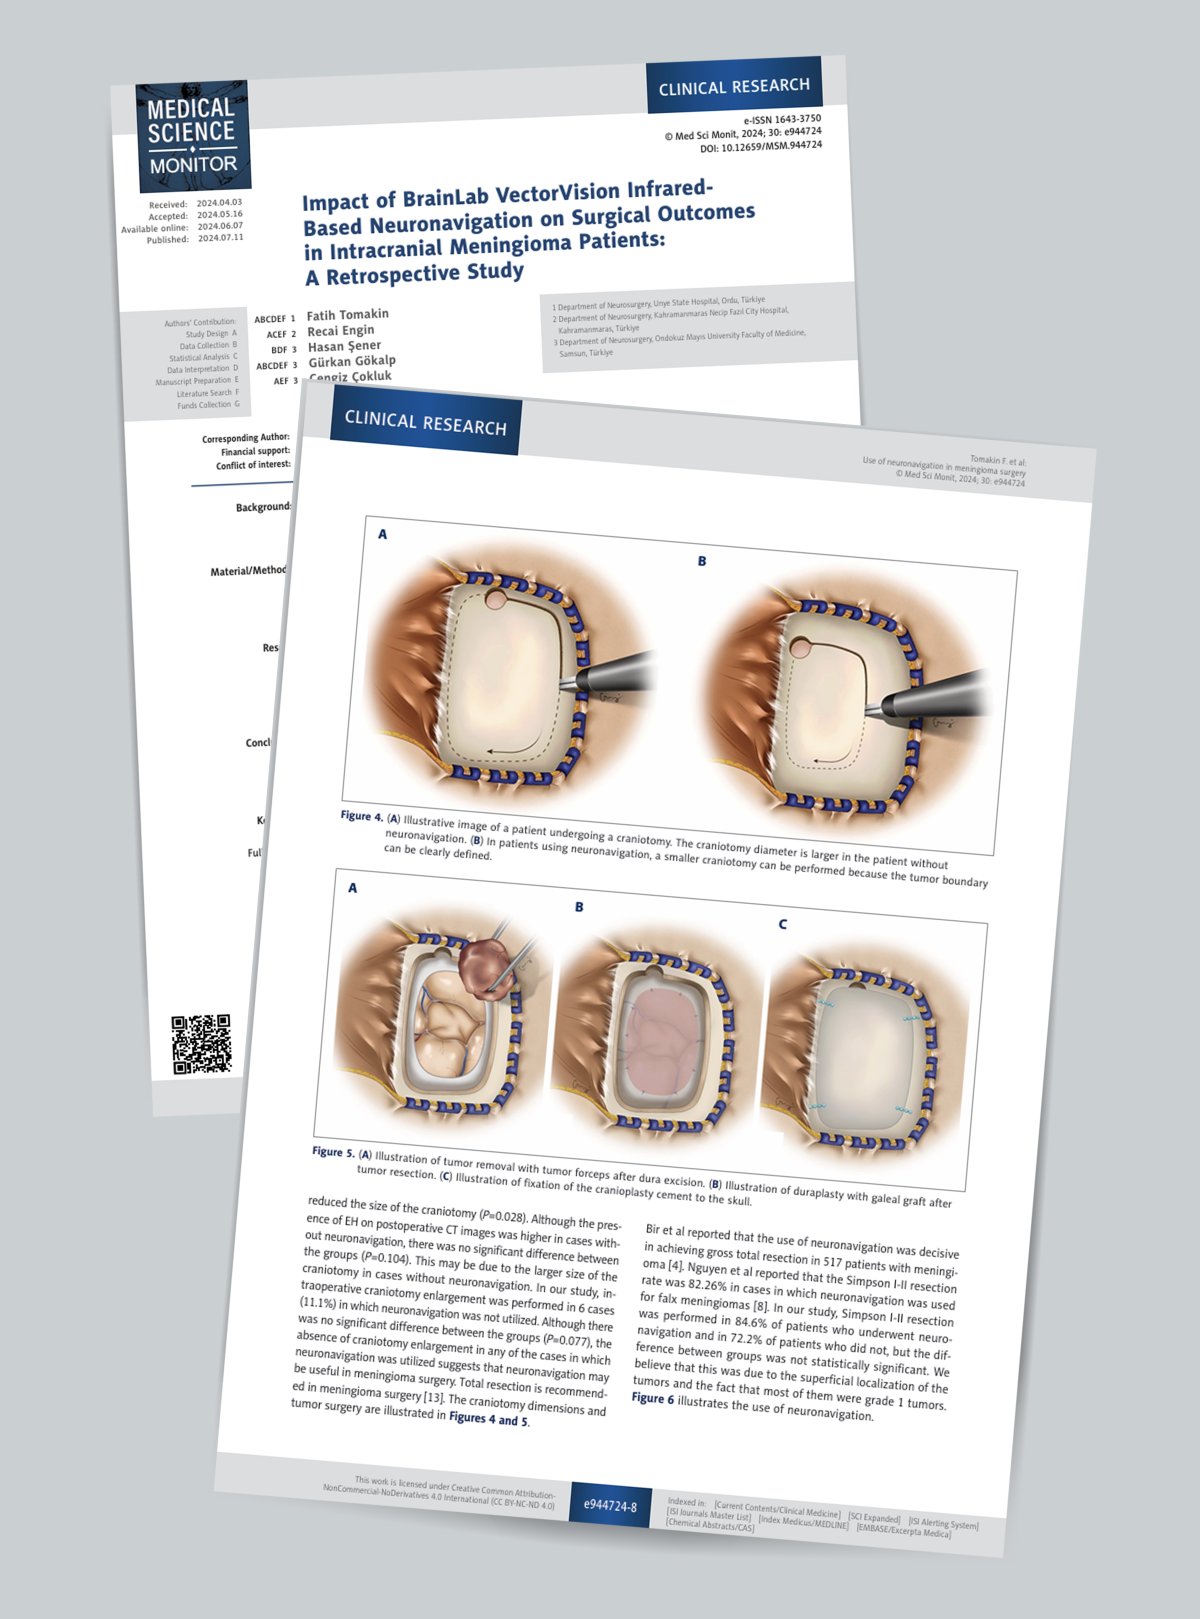

Sanatın estetiğini bilimin kesinliğiyle bir araya getiren Zülal Cangi, medikal ve bilimsel illüstrasyon alanındaki çalışmalarıyla akademik yayınlar, eğitim materyalleri ve çeşitli bilimsel platformlar için görsel içerikler üretmektedir. Amacı, bilimsel bilgiyi yalnızca doğru biçimde aktarmakla kalmayıp, aynı zamanda öğretici ve estetik bir dille görünür kılmaktır.

PORTFÖY